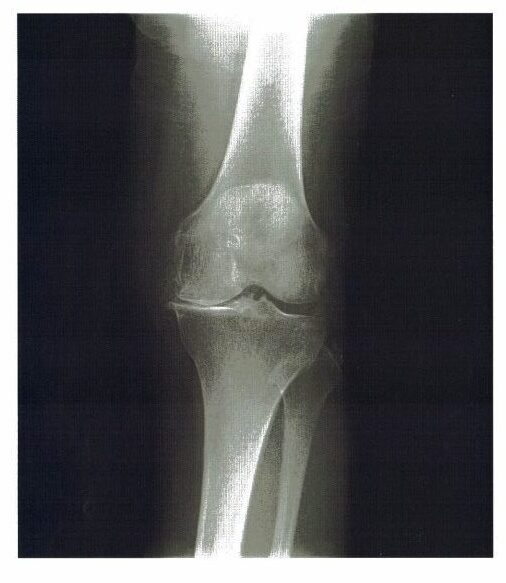

9 73歳の女性。3年前から特に誘因なく歩行時の左膝痛が出現し、徐々に悪化してきたため外来を受診した。左膝の熱感、腫脹なく関節裂隙の圧痛を軽度に認めた。立位のX線写真を下に示す。

・立位のX線写真:膝関節内側の関節裂隙の狭小化あり。